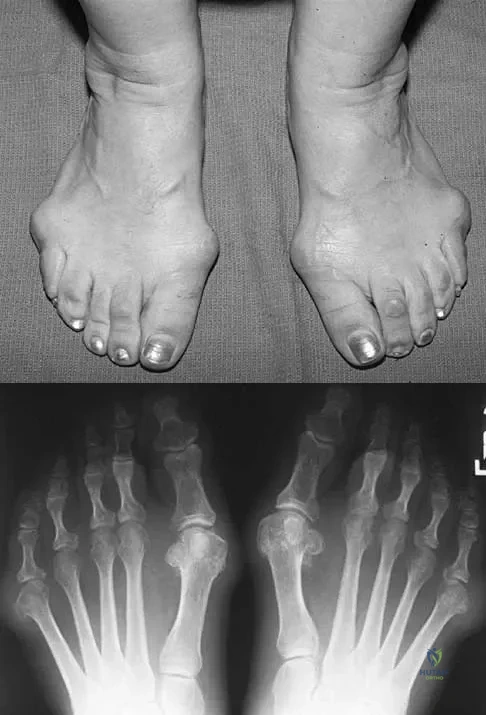

Figures 5a and 5b show the clinical photograph and radiograph of a patient who has difficulty wearing shoes and has persistent symptoms medially and laterally at the first and fifth metatarsophalangeal joints. Because shoe modifications have failed to provide relief, management should now consist of

Explanation